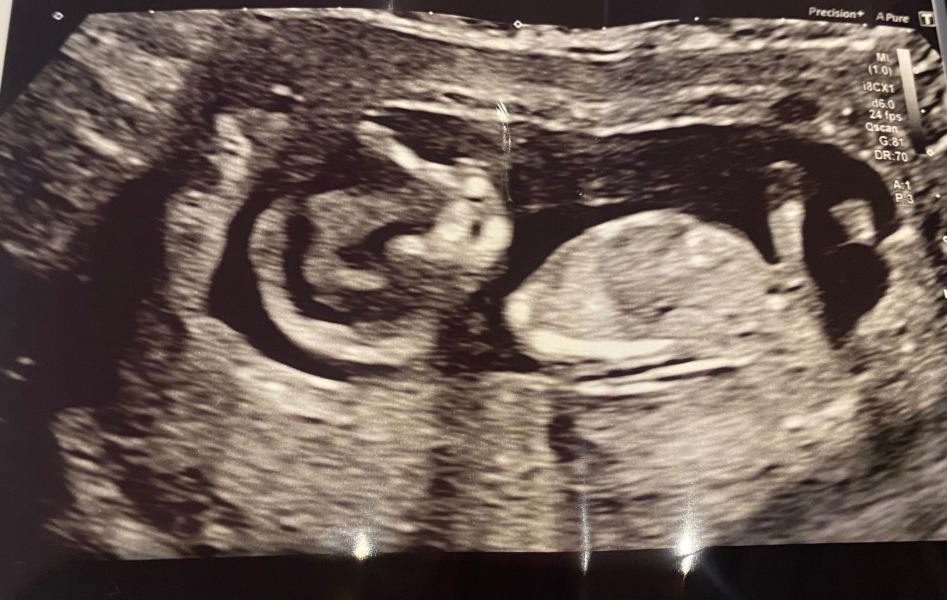

When I went for my 12 week scan, baby upside down and facing wrong way-my measurements were between 3.5 and 4. After jumping around, correct position ranged from 3 to 3:5. They went with 3.6 I guess this is erring on the side of caution.

I would consider TFMR if it is Edward’s or anything that meant the baby had little quality of life. He looked so wiggly and healthy with long legs and nose bone visible. I go from being convinced due to the high risk to doubtful based on the variables of the screening.

I am hoping the scan will show some markers and praying it is false positive or confined to placenta. I can only hope. Nothing too obvious on the scan? I don’t think… currently 14 weeks x

I went for my scan in London today.

Not the best news. Lots consistent with a healthy baby-brain, kidneys, liver, bowel, skeleton.

Fingers and toes fine apart from an extra finger.

However. Heart abnormal, no stomach, facial deformity on the nose, cleft bottom half of face. 😞

It’s consistent with T13 sadly.

I mean, he looks very happy and wiggly in there right now and that’s good.